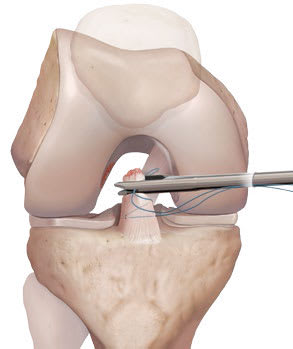

Prenez RDV avec Philippe Paillard pour en savoir plus sur les prothèses genoux. Le ménisque interne sur la partie intérieure du genou et le ménisque externe sur. La rupture d'un ligament croisé antérieur ne nécessite pas d'immobilisation plâtrée, à moins qu'il ne soit réparé chirurgicalement, par suture ou transposition ligamentaire (à l'aide d'un fragment de tendon prélevé sur des muscles voisins ou sur le tendon rotulien) ;.

Reparation Ou Reconstruction Du Ligament Croise Anterieur Du Genou Sous Arthroscopie